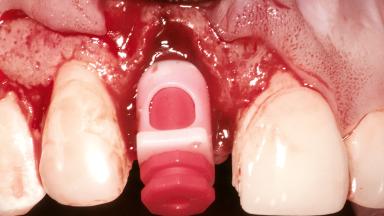

Bone Augmentation Horizontal|Simultaneous

Augmentation Materials Autogenous chips|Membrane

Soft Tissue Grafting Simultaneous

Placement Protocol Early or late implant placement

Bone Volume Deficient horizontally, allowing simultaneous augumentation